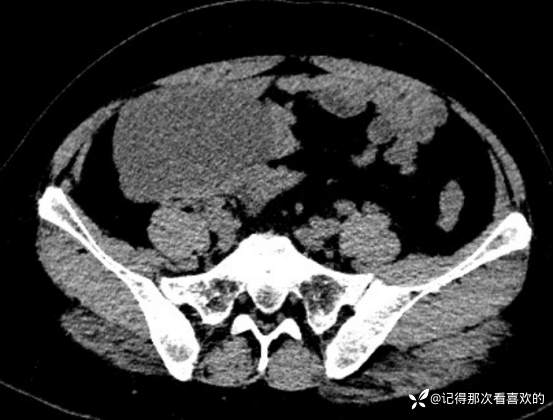

入院后查十二通道常规心电图:1、窦性心律2、逆钟向转位。余相关检验未见明显异常。于2025.05.30在静脉麻醉下行“宫腔镜诊断性刮宫术”,术顺,术后病理(2508387):(宫内容物)子宫内膜息肉。查心脏彩超(Z250530002):三尖瓣轻度反流。双侧下肢深静脉血管彩色多普勒超声(Z250530003):双侧下肢股总静脉反流,考虑双侧下肢深静脉瓣功能不全。经阴道彩超检查(Z250530004):双侧附件区低回声不均团块,考虑MT,建议进一步检查。子宫多发肌瘤。子宫内膜区低回声结节,考虑粘膜下肌瘤可能。宫颈腺体多发囊肿。盆腔MRI增强(MR109286):1.双侧附件区团块状占位,考虑MT,请结合临床。2.子宫肌层内、浆膜下多发肌瘤。3.子宫腔内异常结节灶,粘膜下肌瘤可能。4.盆腔少量积液。5.右侧髂骨内结节灶,性质待定,建议进一步检查。胸部CT(CT384707):1.双肺多发微小结节,建议随诊复查。2.气管憩室。3.扫及右肾结石?新上腹部CT平扫(CT384838):盆腔右侧占位性病变,请结合临床及MRI检查。HPV+TCT:HPV阴性;非典型鳞状上皮细胞(不能明确意义)。2025.06.03行胃肠镜,电子胃十二指肠镜检查(PG25003031):胃体溃疡(待病理);慢性萎缩性胃炎。电子结肠镜检查(PC25002608):结肠多发息肉(内镜下息肉切除+钳除)。快速石蜡病理(2508504):胃体:低分化腺癌,伴少量印戒细胞癌成分,免疫组化结果待补充报告。快速石蜡病理(2508505):降结肠:增生性息肉。